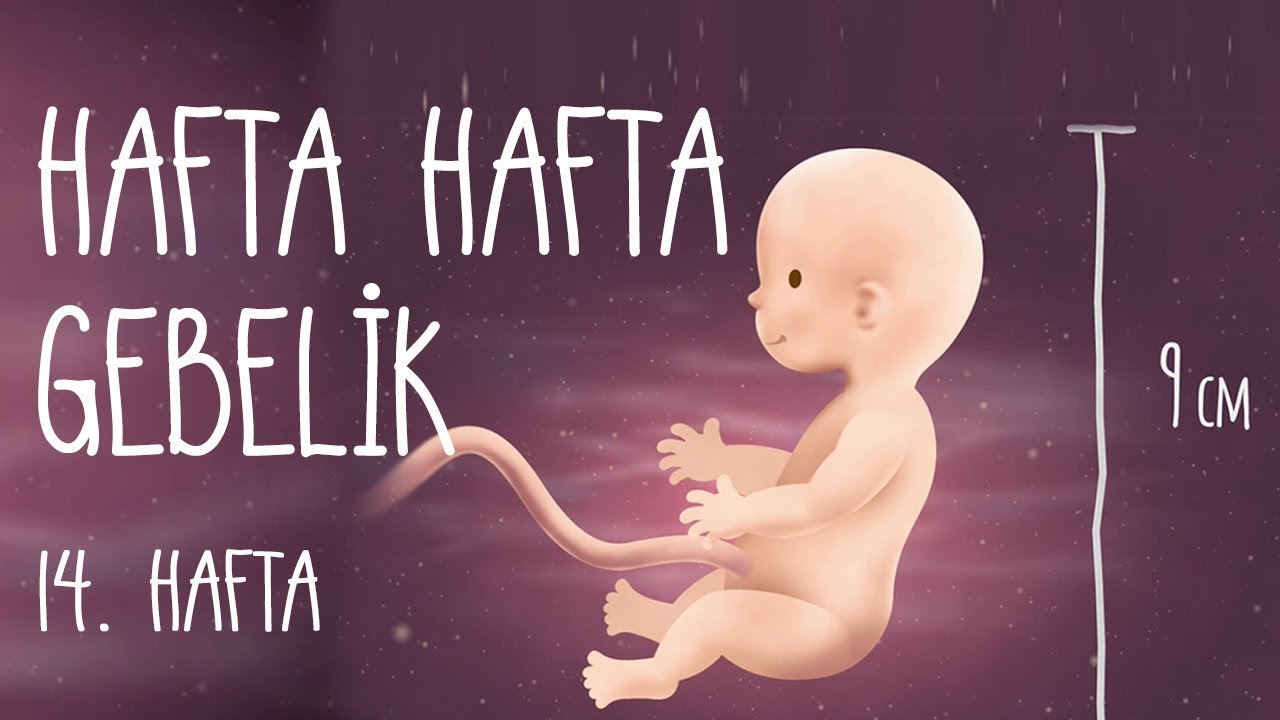

14 Haftalık Gebelik Hafta Hafta Hamilelik Anneysen

Hafta Hafta Gebelik 14. hafta YouTube

14 Haftalık Gebelik Hafta Hafta Hamilelik Anneysen